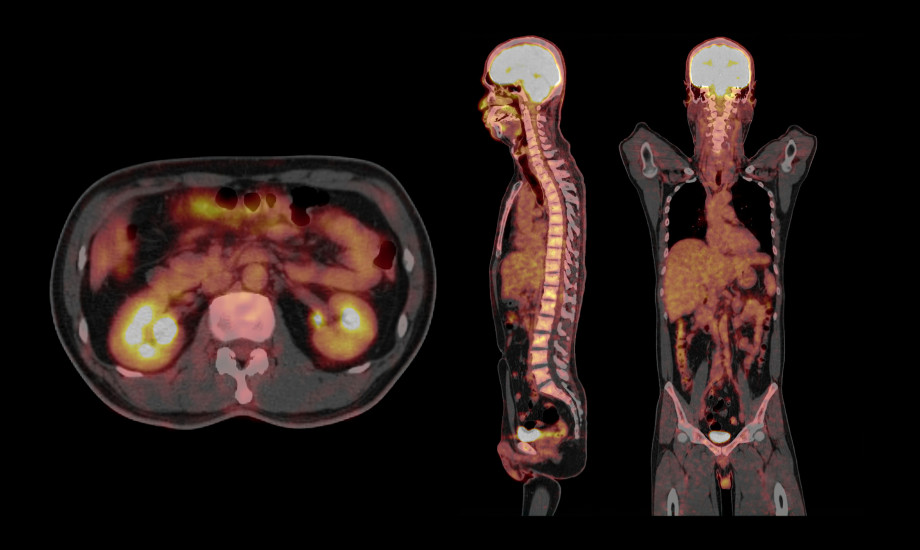

Prostatakarzinom

Frühe PSMA-PET/CT verändert jede dritte Therapieentscheidung

Eine aktuelle Studie zeigt, dass PSMA-PET/CT bereits in der Erstdiagnostik wichtige Zusatzinformationen liefern kann. In rund jedem dritten Fall führte die frühe hochauflösende Bildgebung zu einer veränderten Therapieplanung.